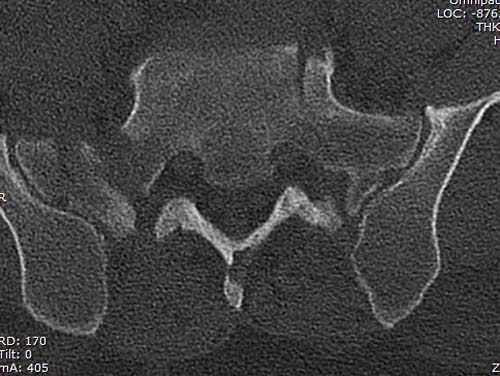

Двухстороннее повреждение крестца и травматическая ампутация бедра, где

неопытной бригадой дежурантов установлен верхний наружный фиксатор для

стабилизации. На третий день ревизия на более стабильный, и

окончательная фиксация. Первые снимки после стабилизации таза, и другие,

где показаны (параллельные) правильная установка на AIIS т.е на месте

прикрепления прямой мышцы бедра. Ампутация закончена костно пластическим

методом.